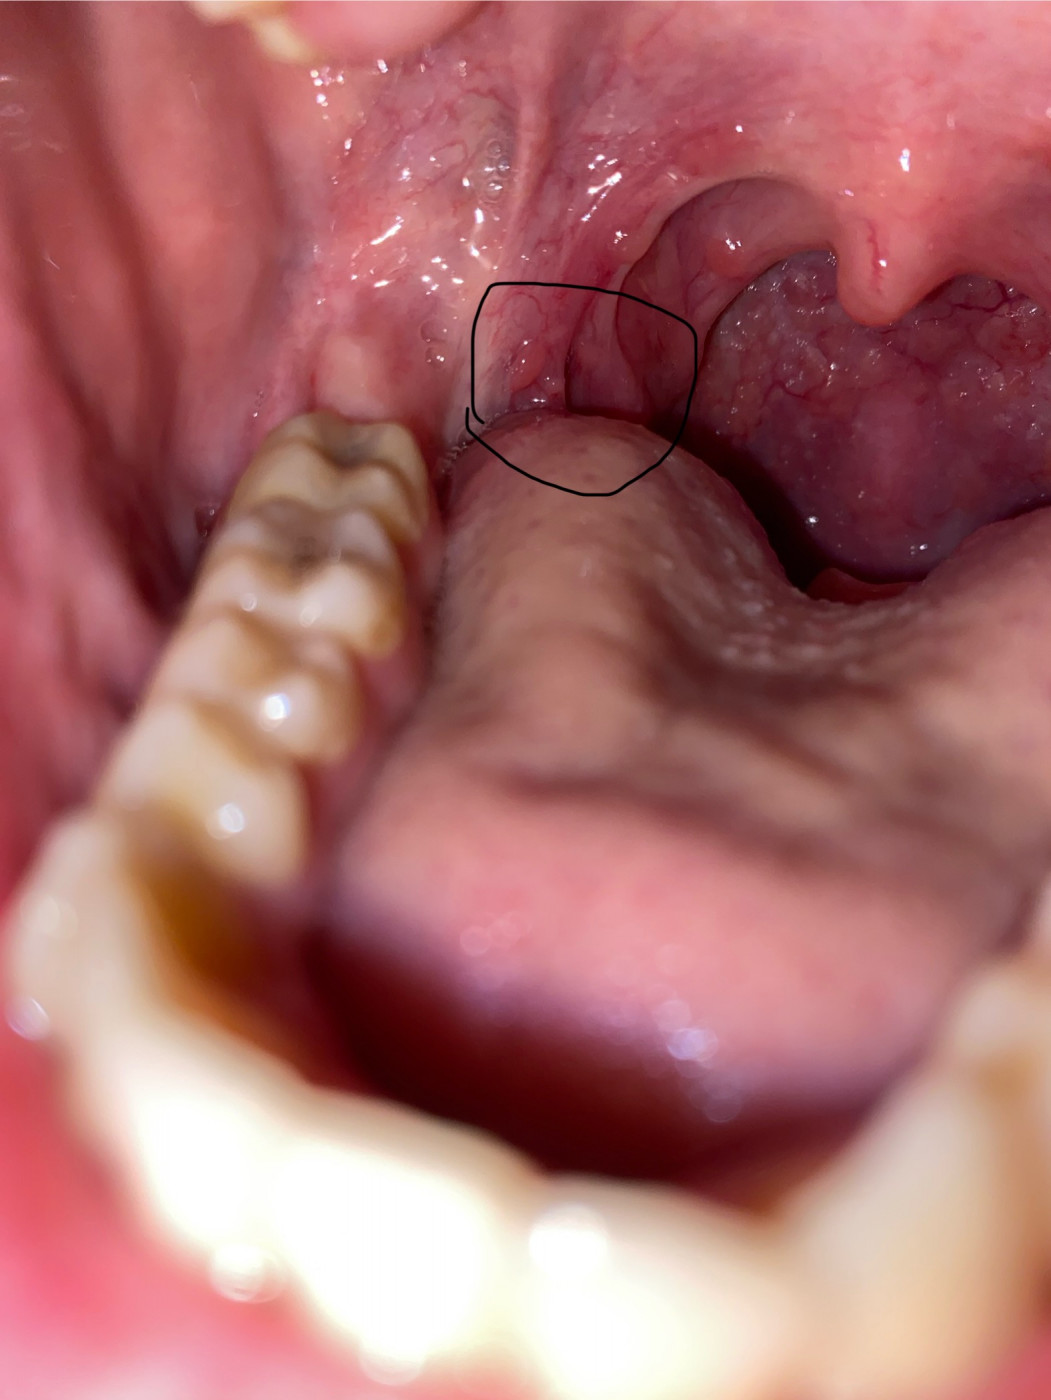

Боль при глотании   0 ответов

Здравствуйте, у меня сегодня началась боль в горле при глотании. Посветив фонариком себе в рот, я увидела красные язычок и небно-язычную дужку, также стекала слизь жёлтая в горло. Я не особо обратила на это внимание, рассосала одну таблетку грамидина, и на этом всё. Сейчас вечер, мне ещё стало больнее глотать, говорить не могу, больно в горле и отдаёт…